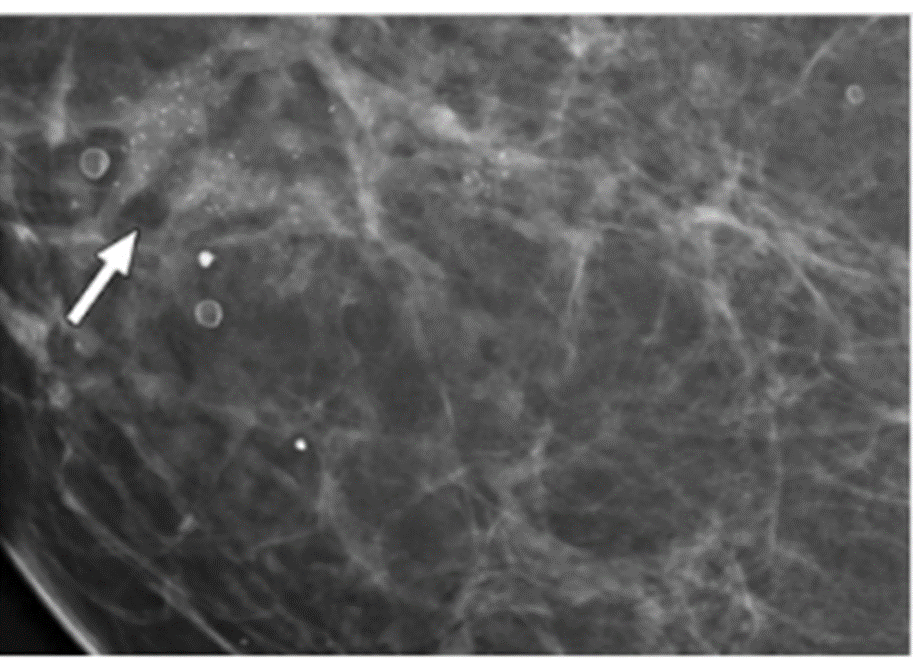

Khối mờ có nhiều nốt vi vôi hoá không đồng nhất, gián đoạn: nghi ngờ ung thư vú

Đây là phương pháp chụp X-quang vú đặc biệt, đóng vai trò quan trọng trong tầm soát ung thư vú. Đây là thủ thuật sử dụng tia X cường độ thấp chiếu vào các mô tuyến vú để thu lại hình ảnh tại tuyến vú. Qua hình ảnh thu được từ chụp X-quang vú, bác sĩ có thể phát hiện các bất thường và khối u ở giai đoạn sớm ngay cả khi bệnh nhân chưa phát hiện, sờ thấy.

Kỹ thuật chụp Mammography có những ưu điểm vượt trội như thời gian thực hiện nhanh, không xâm lấn, kết quả chính xác, chi phí hợp lý,... Nhiều nghiên cứu cho thấy chụp Mammography giúp giảm tỷ lệ tử vong của ung thư vú khoảng 30%. Vì vậy, các chuyên gia ung bướu ưu tiên chỉ định kỹ thuật chẩn đoán hình ảnh này. Những phụ nữ trên 40 tuổi nên chụp Mamo vú 1 - 2 lần/năm.